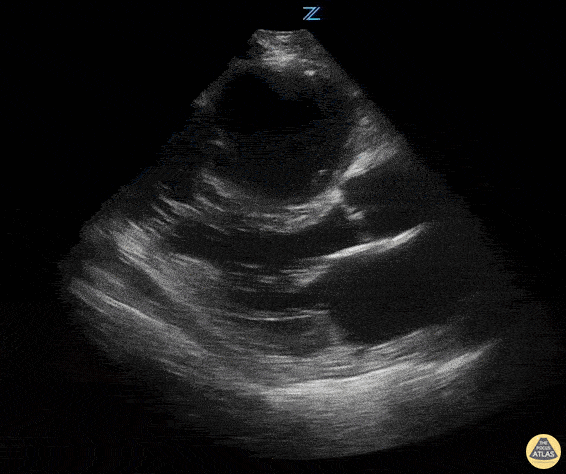

100 year old patient presented with dyspnea. CXR showed "atelectasis vs. pneumonia." No leukocytosis or fever seen. She began to have episodes of hypotension. Before giving fluids, an echo was performed...... She had chronic RV failure with an acute exacerbation. Notice severe RV enlargement seen in this PSLA view. John Bowling, DO, Cleveland Clinic Akron General, @BModeBowling